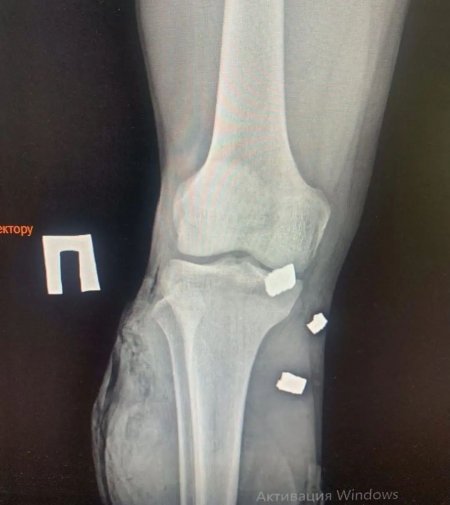

24 листопада під час обстрілу в районі Бахмута Назар отримав тяжкі множинні поранення ніг. Його екстрено прооперували у Дніпрі. Наразі кременчужанин перебуває у госпіталі в Києві.

На його реабілітацію та лікування необхідні фінансові затрати. Лікарі поки ніяких прогнозів не дають, адже уламків у ногах багато.